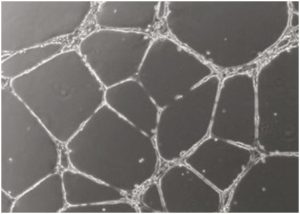

Evercyte has developed novel telomerized podocyte and microvascular endothelial cell lines that are balanced in growth and differentiation as they show functions of the corresponding primary cell counterparts concomitant with an unlimited growth.

The combination of these cell types allows researchers to set up a glomerular filtration barrier model. This can be used in three different ways:

Highly differentiated immortalized human somatic cells are of ever increasing importance as in vitro test systems in various fields of biomedicine, toxicology and biotechnology. Although normal somatic cells maintain a phenotype similar to the corresponding cells in vivo, the application of these cells is limited due to their finite life span. In contrast, tumor cells can be grown without limitation but lacking essential characteristics.